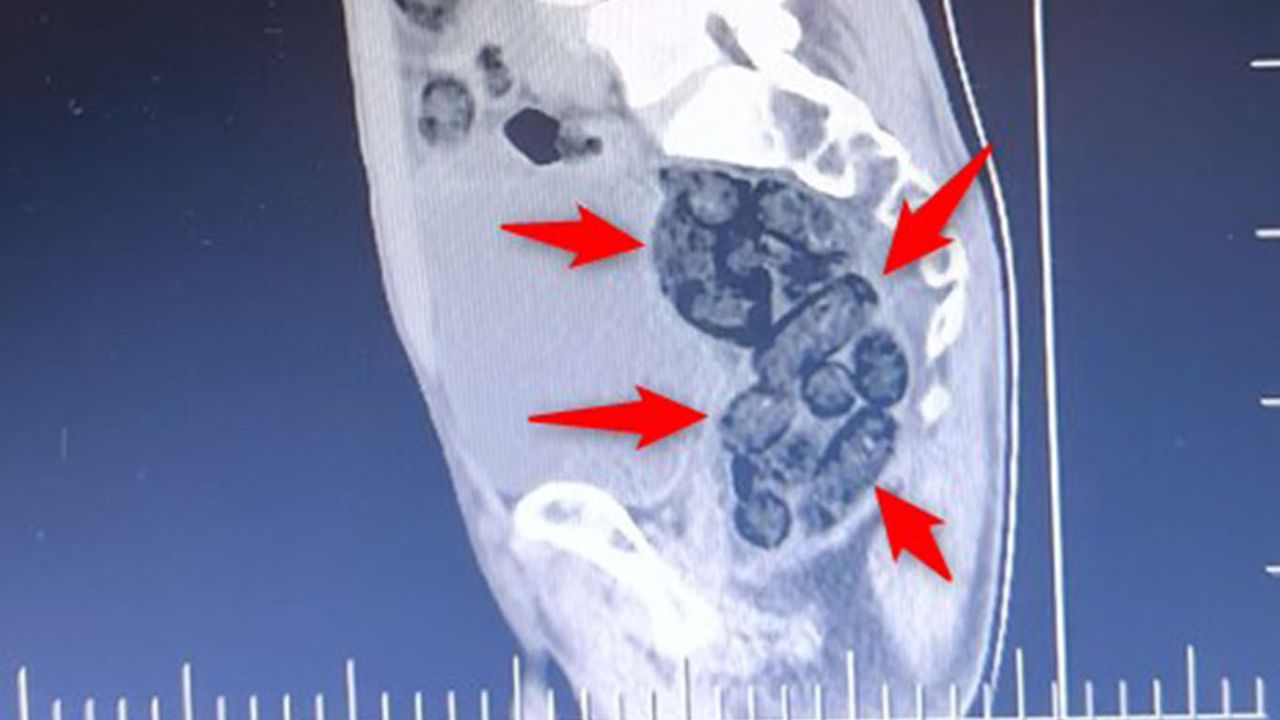

İl girişinde durdurulan bir otobüste yolcu olarak bulunan yabancı uyruklu bir şahıs üzerinde yapılan kontrollerde, şahsın midesinde 64 parça halinde toplam 472 gram metamfetamin maddesi tespit edilerek ele geçirildi.